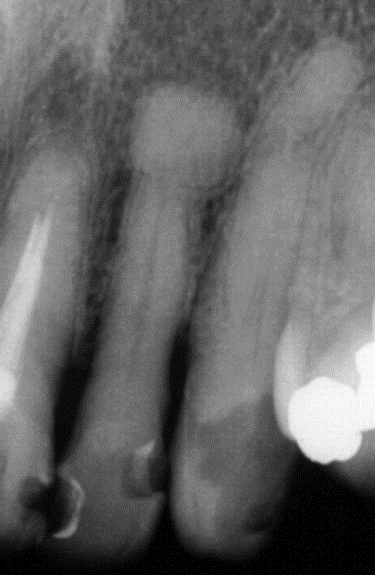

2. (Select ONE OR MORE correct answers)

The radiograph shows evidence of